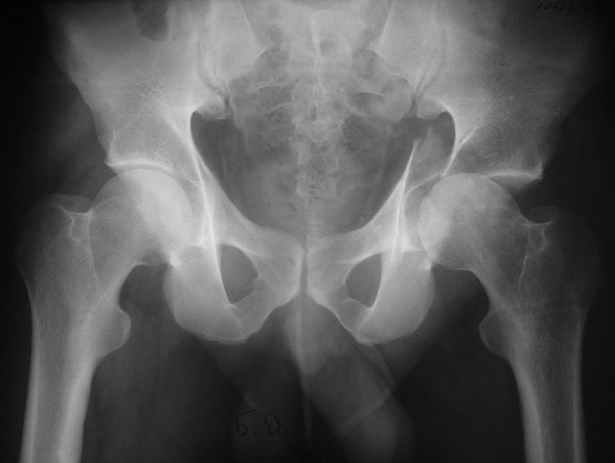

Anatoly F Lazarev 03 Сентябрь 2004, 22:18

Женя! Класный перелом. Отлично репонируется изнутри таза, но лучше фиксированть сзади. Классический перелом для двустороннего доступа.

Anatoly F Lazarev 03 Сентябрь 2004, 22:39

Высылаю пример еще одного случая, остеосинтез пластиной из подвздошного доступа.